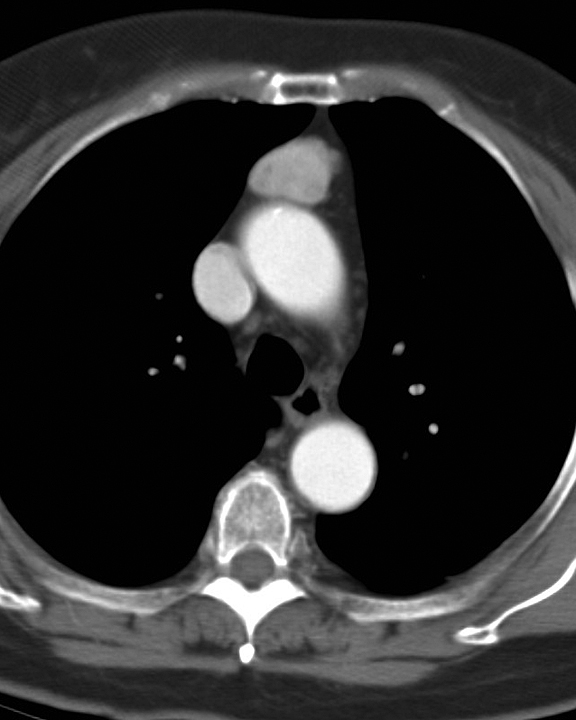

Case 8c Thymoma CT